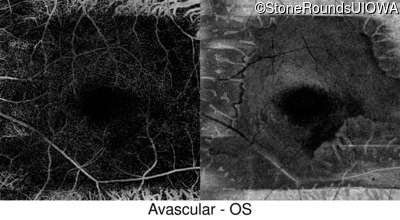

Optical Coherence Tomography - Left - 20/12.5 -2

Exemplar / OCT Stack

OCT Stack